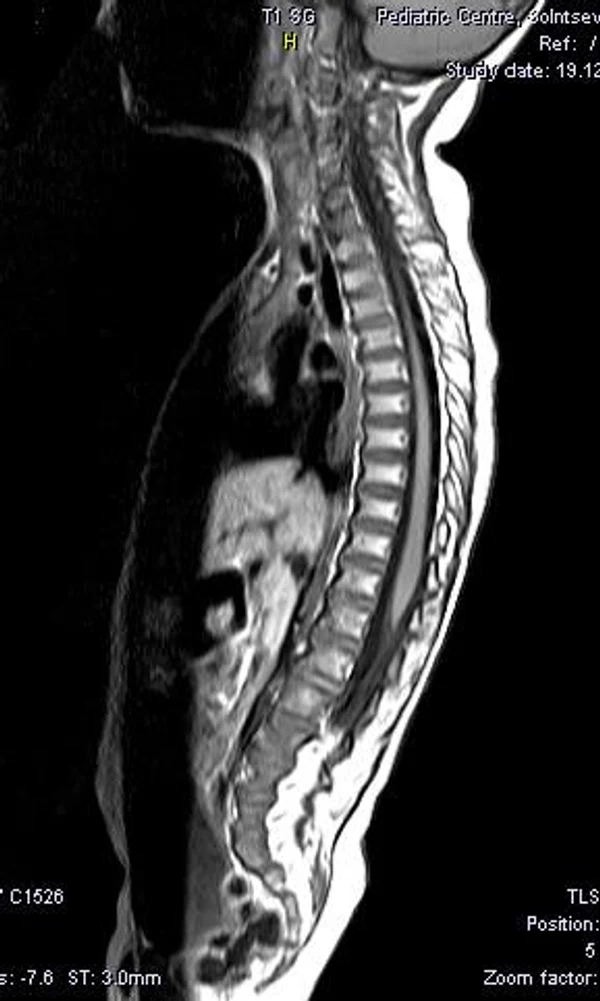

В качестве примера приведены 2 случая хирургического лечения новорожденных с врожденными опухолями головного мозга и позвоночного канала. У новорожденной девочки опухоль (хориодпапиллома) располагалась в области треугольника правого бокового желудочка (рис. 28 а, б). В возрасте 2-х недель жизни опухоль удалена. По данным МРТ головы с внутривенным введением контрастного препарата выполненной через 2 дня после операции опухоль удалена тотально (рис. 28 в). Послеоперационных осложнений не наблюдалось. У второго пациента 2-х нед. жизни врождённая опухоль (нейробластома) располагалась в позвоночном канале на уровне Th10-L3 позвонков (рис. 29 а) и распространялась в забрюшинное пространство. Клиническая картина заболевания складывалась из нижнего вялого парапареза и нарушения функции тазовых органов. Во время операции остистые отростки Th 11-L3 позвонков рассечены по средней линии. Дужки 6 данных позвонков надломлены и разведены в стороны. Опухоль располагалась экстрадурально, отделена от дорзальной поверхности дурального мешка и корешков спинно-мозговых нервов, после чего полностью удалена из позвоночного канала. Половинки дужек позвонков сведены к средней линии и сшиты между собой. Опухолевый узел в забрюшинном пространстве через 2 нед. удален онкологами. Через год после операции по данным МРТ рецидива опухоли нет (рис. 29 б). При спондилографии дефектов задней стенки и деформаций позвоночника не выявлено (рис. 29 в). Мальчик ходит, мочу и кал удерживает.